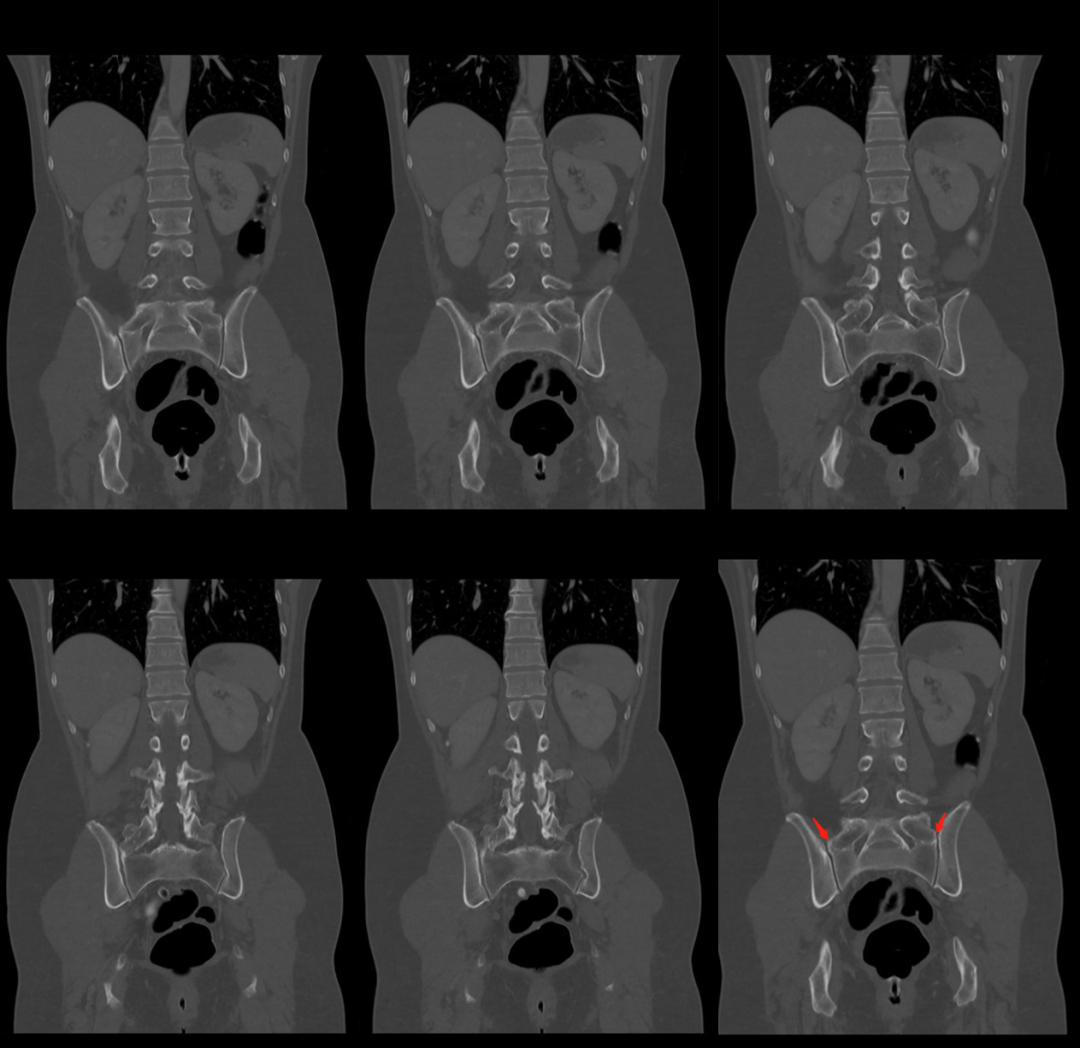

1984年,Castellvi 提出LSTV分类系统将移行椎分为Ⅰ-Ⅳ型。

Ia型(单侧)和Ib型(双侧):横突肥大宽度超过19mm

IIa型(单侧)和IIb型(双侧):横突与骶骨相接触形成假关节

IIIa型(单侧)和IIIb型(双侧),横突与骶骨发生骨性融合

IV型:一侧横突与骶骨形成假关节,另一侧形成骨性融合

目前,腰骶移行椎以 Castellvi 的分类方法最为常用。其主要根据横突形态及其与骶骨、髂骨是否融合或形成假关节而分为 4 型,Ⅰ、Ⅱ、Ⅲ型又根据单、双侧分为A、B两个亚型。

正常I型:主要为腰5横突发育不良,横突宽度大于19mm,并将其分为两个亚型Ia(单侧横突发育不良)或Ib(双侧横突发育不良)

L5 右侧横突肥大,为 Ⅰa 型

L5 双侧横突肥大,为Ⅰb 型

II型:表现为不完全的腰椎骶化,具有增宽的横突,并且和骶骨形成假关节,并将其分为两个亚型IIa(单侧关节形成)或IIb(双侧关节形成)

L5 左侧横突肥大,假关节形成,为 Ⅱa 型

L5 双侧横突肥大,假关节形成,为 Ⅱb 型

III型:单侧(IIIa)或双侧(IIIb)腰椎完全骶化,腰5横突与骶骨完全骨性融合

L5 右侧横突肥大与骶骨发生骨性融合,为 Ⅲa 型

L5 双侧横突与骶骨骨性融合,为 Ⅲb 型IV型:一侧为II型即腰5横突与骶骨形成假关节,对侧为III型即腰5横突与骶骨形成骨性融合

IV 型即混合型:L5 双侧横突肥大,一侧与骶骨相接触为Ⅱ型表现,另一侧与骶骨形成骨性融合为Ⅲ型移行椎一般不引起症状,但是这种畸形可影响脊柱的稳定并逐渐产生症状,移行椎较正常椎体潜在着更多不稳。由于负重及运动不平衡,而引起腰痛。